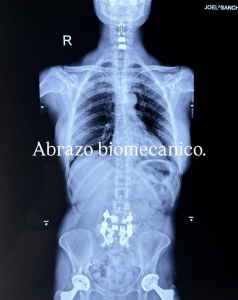

La imagen, publicada en Instagram, muestra la magnitud de la intervención y lo que parece ser una prótesis.

La cantante acompañó la fotografía con la frase “Abrazo biomecánico” y no añadió más detalles sobre el procedimiento.

La reciente cirugía de emergencia habría incluido piezas de titanio en la columna. Aunque no se han dado más detalles, todo indica que su recuperación avanza favorablemente.